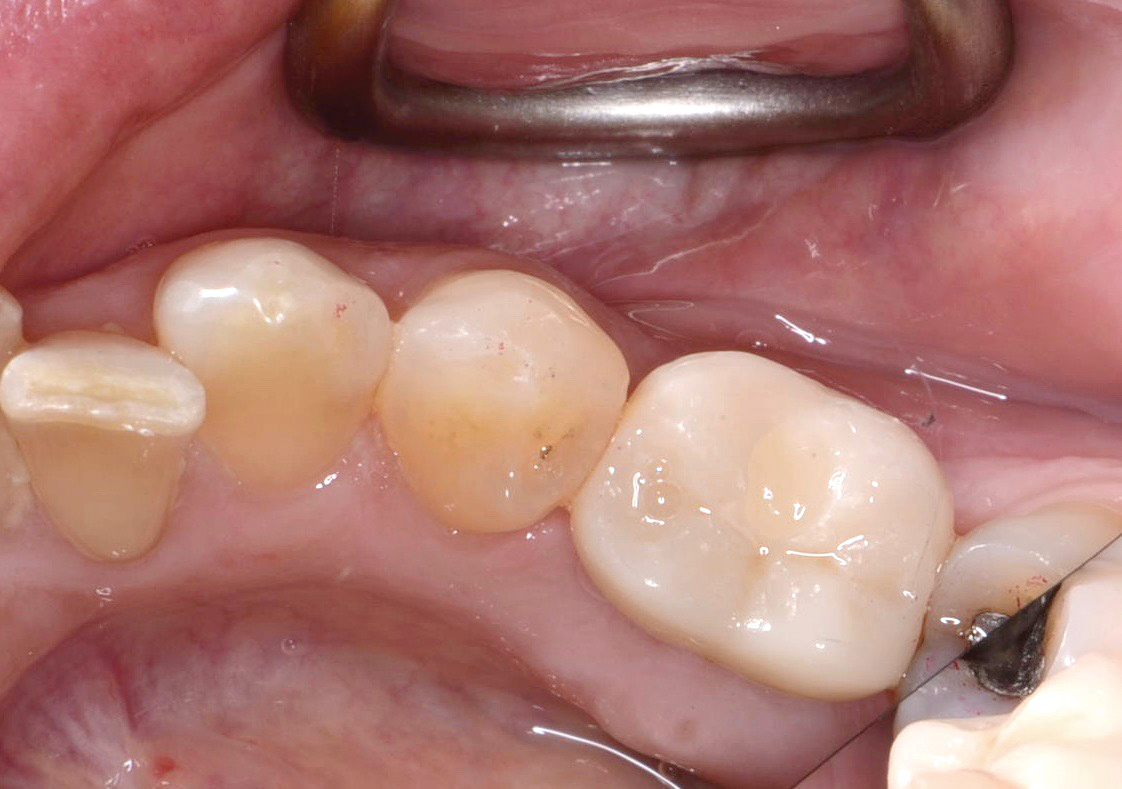

Fig 8. Loss of restoration and subsequent tissue overgrowth from broken abutment screw as shown in the radiograph (Fig 9).

Figure 8

Fig 9. Radiograph depicting fractured screw inside of the implant.

Figure 9

Fractured screws are challenging to retrieve, particularly when they are abutment screws. If the screw head is accessible, a hemostat can be used to remove it. However, when the screw breaks inside the implant (Figure 8 and Figure 9), removal can be highly complicated in order not to damage the implant’s internal threads. Therefore, many implant manufacturers have developed screw-retrieval kits. Because it is critical to be able to visualize the area, magnification using loupes and a surgical microscope may be necessary.8 Additional methods can be used to remove the fractured screw. A ¼ round bur set on a high speed can be used by lightly activating it, touching only the side of the screw. After repeating this technique several times, the screw may be able to be backed out with an explorer tip. Ultrasonic tips with copious irrigation may also dislodge the screw.7,20 In cases in which this fails, a small slot can be made in the head of the screw to back it out.21 If screw threads have been damaged during retrieval, they may be retapped using a tool obtained only from the implant manufacturer.7